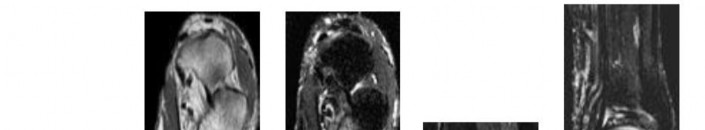

DISCUSSION: The MRI scan shows a coronal oblique view of a partial-

thickness bursal surface supraspinatus tear. Partial-thickness rotator cuff tears are a common cause of shoulder pain, with articular-sided tears two to three times more common than bursal-sided tears. The articular surface of the supraspinatus is intact in this image; therefore, no partial articular or full-thickness tear exists. The superior labrum is seen at the top of the glenoid with no tear. Internal impingement affects the articular surface of the rotator cuff in abduction and external rotation, causing labral tearing and partial articular-sided rotator cuff tears. The Preferred Response to Question # 5 is 3.

4. # Figure 6 shows a sagittal oblique MRI scan of a right shoulder. The asterisk indicates what anatomic structure?

DISCUSSION: The asterisk indicates the subscapularis. The sagittal oblique MRI image shown is taken at the level of the coracoid, which

allows orientation of the anterior and posterior aspects of the shoulder. Evaluation of the rotator cuff in this plane is important to determine the amount of muscle atrophy and fatty infiltration, which may determine prognosis for rotator cuff repair. The supraspinatus is superior to the glenoid and the infraspinatus; teres minor and teres major are posterior. Prefe Res is 1.